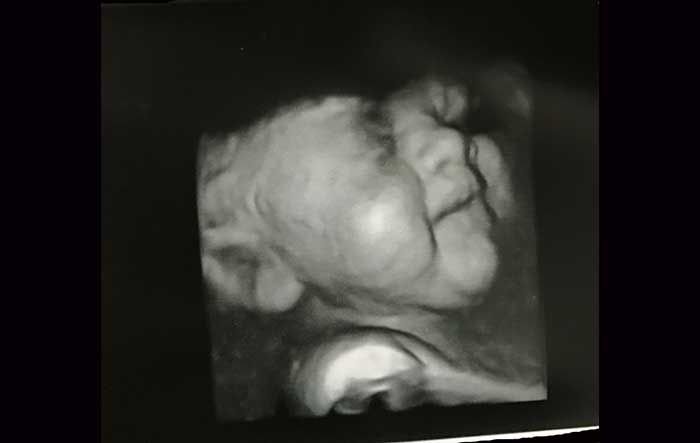

I couldn’t tell from the ultrasound images they showed us, but to them, it was clear that our baby girl had something called duodenal atresia. A hundred years ago, this would have been an automatic death sentence. Babies with this condition have a blockage in their intestine that keeps them from eating once they’re born. In the womb, it causes amniotic fluid to build up to tremendous levels.